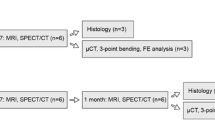

After one week of acclimatization, the animals were anaesthetized by an intraperitoneal injection of 100 mg/kg ketamine 10% and 7 mg/kg xylazine 2% hydrochloride. The left leg was positioned laterally and fixed using a wooden stick and adhesive tape. A 1.5 cm thick wax bolus was positioned over the left tibia and a total dose of 30 Gy was administered in one session, using a linear accelerator (Varian Clinac® 600C S/N 0310, Palo Alto, CA, USA). The left tibiae were designated to the irradiated group and the right tibia that did not receive irradiation, were assigned to the non-irradiated group. The HBO sessions started 30 days after IR in ten animals, and therapies were performed daily for 1 week in a cylindrical pressure chamber (Ecobar 400, Ecotec Equipamentos e Sistemas Ltda®, Mogi das Cruzes, SP, Brazil) at 250 kPa for 90-min sessions after compression (Fig. 1).

The animals were euthanized 37 days after irradiation by intraperitoneal injection with sodium thiopental and lidocaine, followed by cervical dislocation, in compliance with the principles of the Universal Declaration on Animal Welfare. The tibiae were separated into four groups (n = 10): from animals without HBO - right tibia Non-irradiated (noIRnoHBO) and left tibia Irradiated (IRnoHBO); and from animals with HBO - right tibiae Non-irradiated (noIRHBO) and left tibia Irradiated (IRHBO). The tibiae were removed by disarticulation, immediately placed in a gauze with physiological saline solution and were stored 2 weeks in freezer storage at − 20 °C. Twenty-four hours before the analysis, the tibiae were defrosted and placed in phosphate buffered saline until analysis.